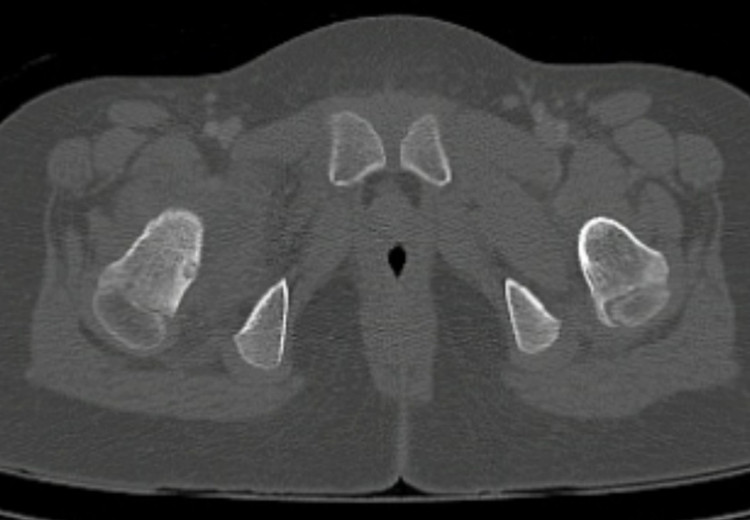

Sau khi thăm khám tại nhiều bệnh viện tuyến tỉnh và trung ương, các bác sĩ xác định nguyên nhân là do một u xương lành tính (osteoid osteoma). Kích thước khối u chỉ 5mm nhưng nằm sâu ở mặt sau và trong của cổ xương đùi , nằm trong bao khớp và sát với bề mặt của khớp háng – vị trí rất khó tiếp cận.

Khối u nằm ở một vị trí cực kỳ khó: mặt sau và trong của cổ xương đùi bên phải, hoàn toàn trong bao khớp. Phẫu thuật gần như không thể vì nếu mổ mở để lấy u, cháu bé có nguy cơ cao bị tổn thương mạch máu nuôi xương, dẫn tới hoại tử chỏm xương đùi, thậm chí phải thay khớp háng khi còn rất nhỏ tuổi.

Sau khi hội chẩn liên chuyên khoa, đội ngũ bác sĩ tại Trung tâm Điện quang can thiệp – Bệnh viện Đại học Y Hà Nội đã thống nhất lựa chọn phương pháp can thiệp ít xâm lấn đốt u bằng sóng cao tần (RFA) dưới hướng dẫn của hệ thống chụp mạch số hóa xóa nền (DSA) kết hợp với CT hình nón (Cone-Beam CT) để định vị chính xác khối u và đưa kim đốt đúng vị trí mà không làm tổn thương mạch máu quanh cổ xương đùi.